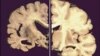

New research suggests that a brain protein that has changed form may be the cause of brain disorders -- including Alzheimer’s Disease. Researchers say they have developed a treatment that may cause the protein to return to its original form, preventing the disease from developing or reversing the effects of the damage in people who already suffer from Alzheimer’s.

Researchers at Beth Israel Deaconess Medical Center in Boston, Massachusetts, found that the shape of the protein -- which is called “tau” -- is changed by severe injuries to the brain. The scientists say when people are hit in the head many times, they develop a condition called chronic traumatic encephalopathy, or CTE.